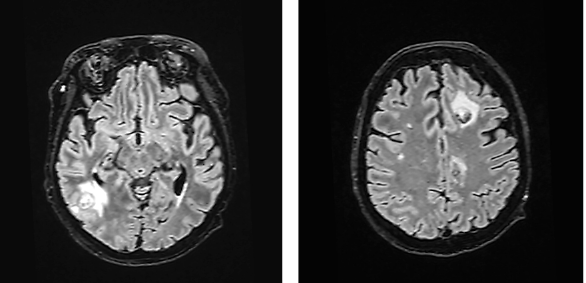

The patient’s condition deteriorated during transportation, requiring re-intubation. Neurosurgical intervention was not considered viable. Consequently, the antibiotic regimen was expanded to include Ceftriaxone, Vancomycin, Metronidazole, and Sulfamethoxazole-Trimethoprim, targeting a broader spectrum of pathogens potentially responsible for brain abscesses. Despite plans to conduct diagnostic tests for HIV, syphilis, toxoplasmosis, and Listeria from the abscess aspirates, the patient’s condition rapidly deteriorated, becoming critically unstable. This acute decline was marked by severe respiratory insufficiency and profound bradycardia, necessitating immediate cardiopulmonary resuscitation (CPR) and the urgent administration of Atropine. Finally, due to prolonged intubation, it was decided to form a tracheostomy. Subsequent MRI showed a reduction in the abscess size (Fig. 3), and the patient was transferred to the Neurology Department for continued care.

During the consultation in the Neurology Department, it was decided not to perform a puncture of the brain abscesses due to the potential risk of developing secondary meningitis. Antibiotic therapy was continued to cover possible pathogens of the brain abscesses. The patient’s condition and muscle strength improved during the course of treatment. The dynamics of the brain abscesses were positive, and the laboratory inflammation markers decreased. During the course of treatment, the patient had three episodes of loss of consciousness, which were considered to be of epileptic origin. Levetiracetam 750mg/day was prescribed. Antibiotic therapy with Vancomycin, Ceftriaxone, and Metronidazole was ongoing (already in week 15).